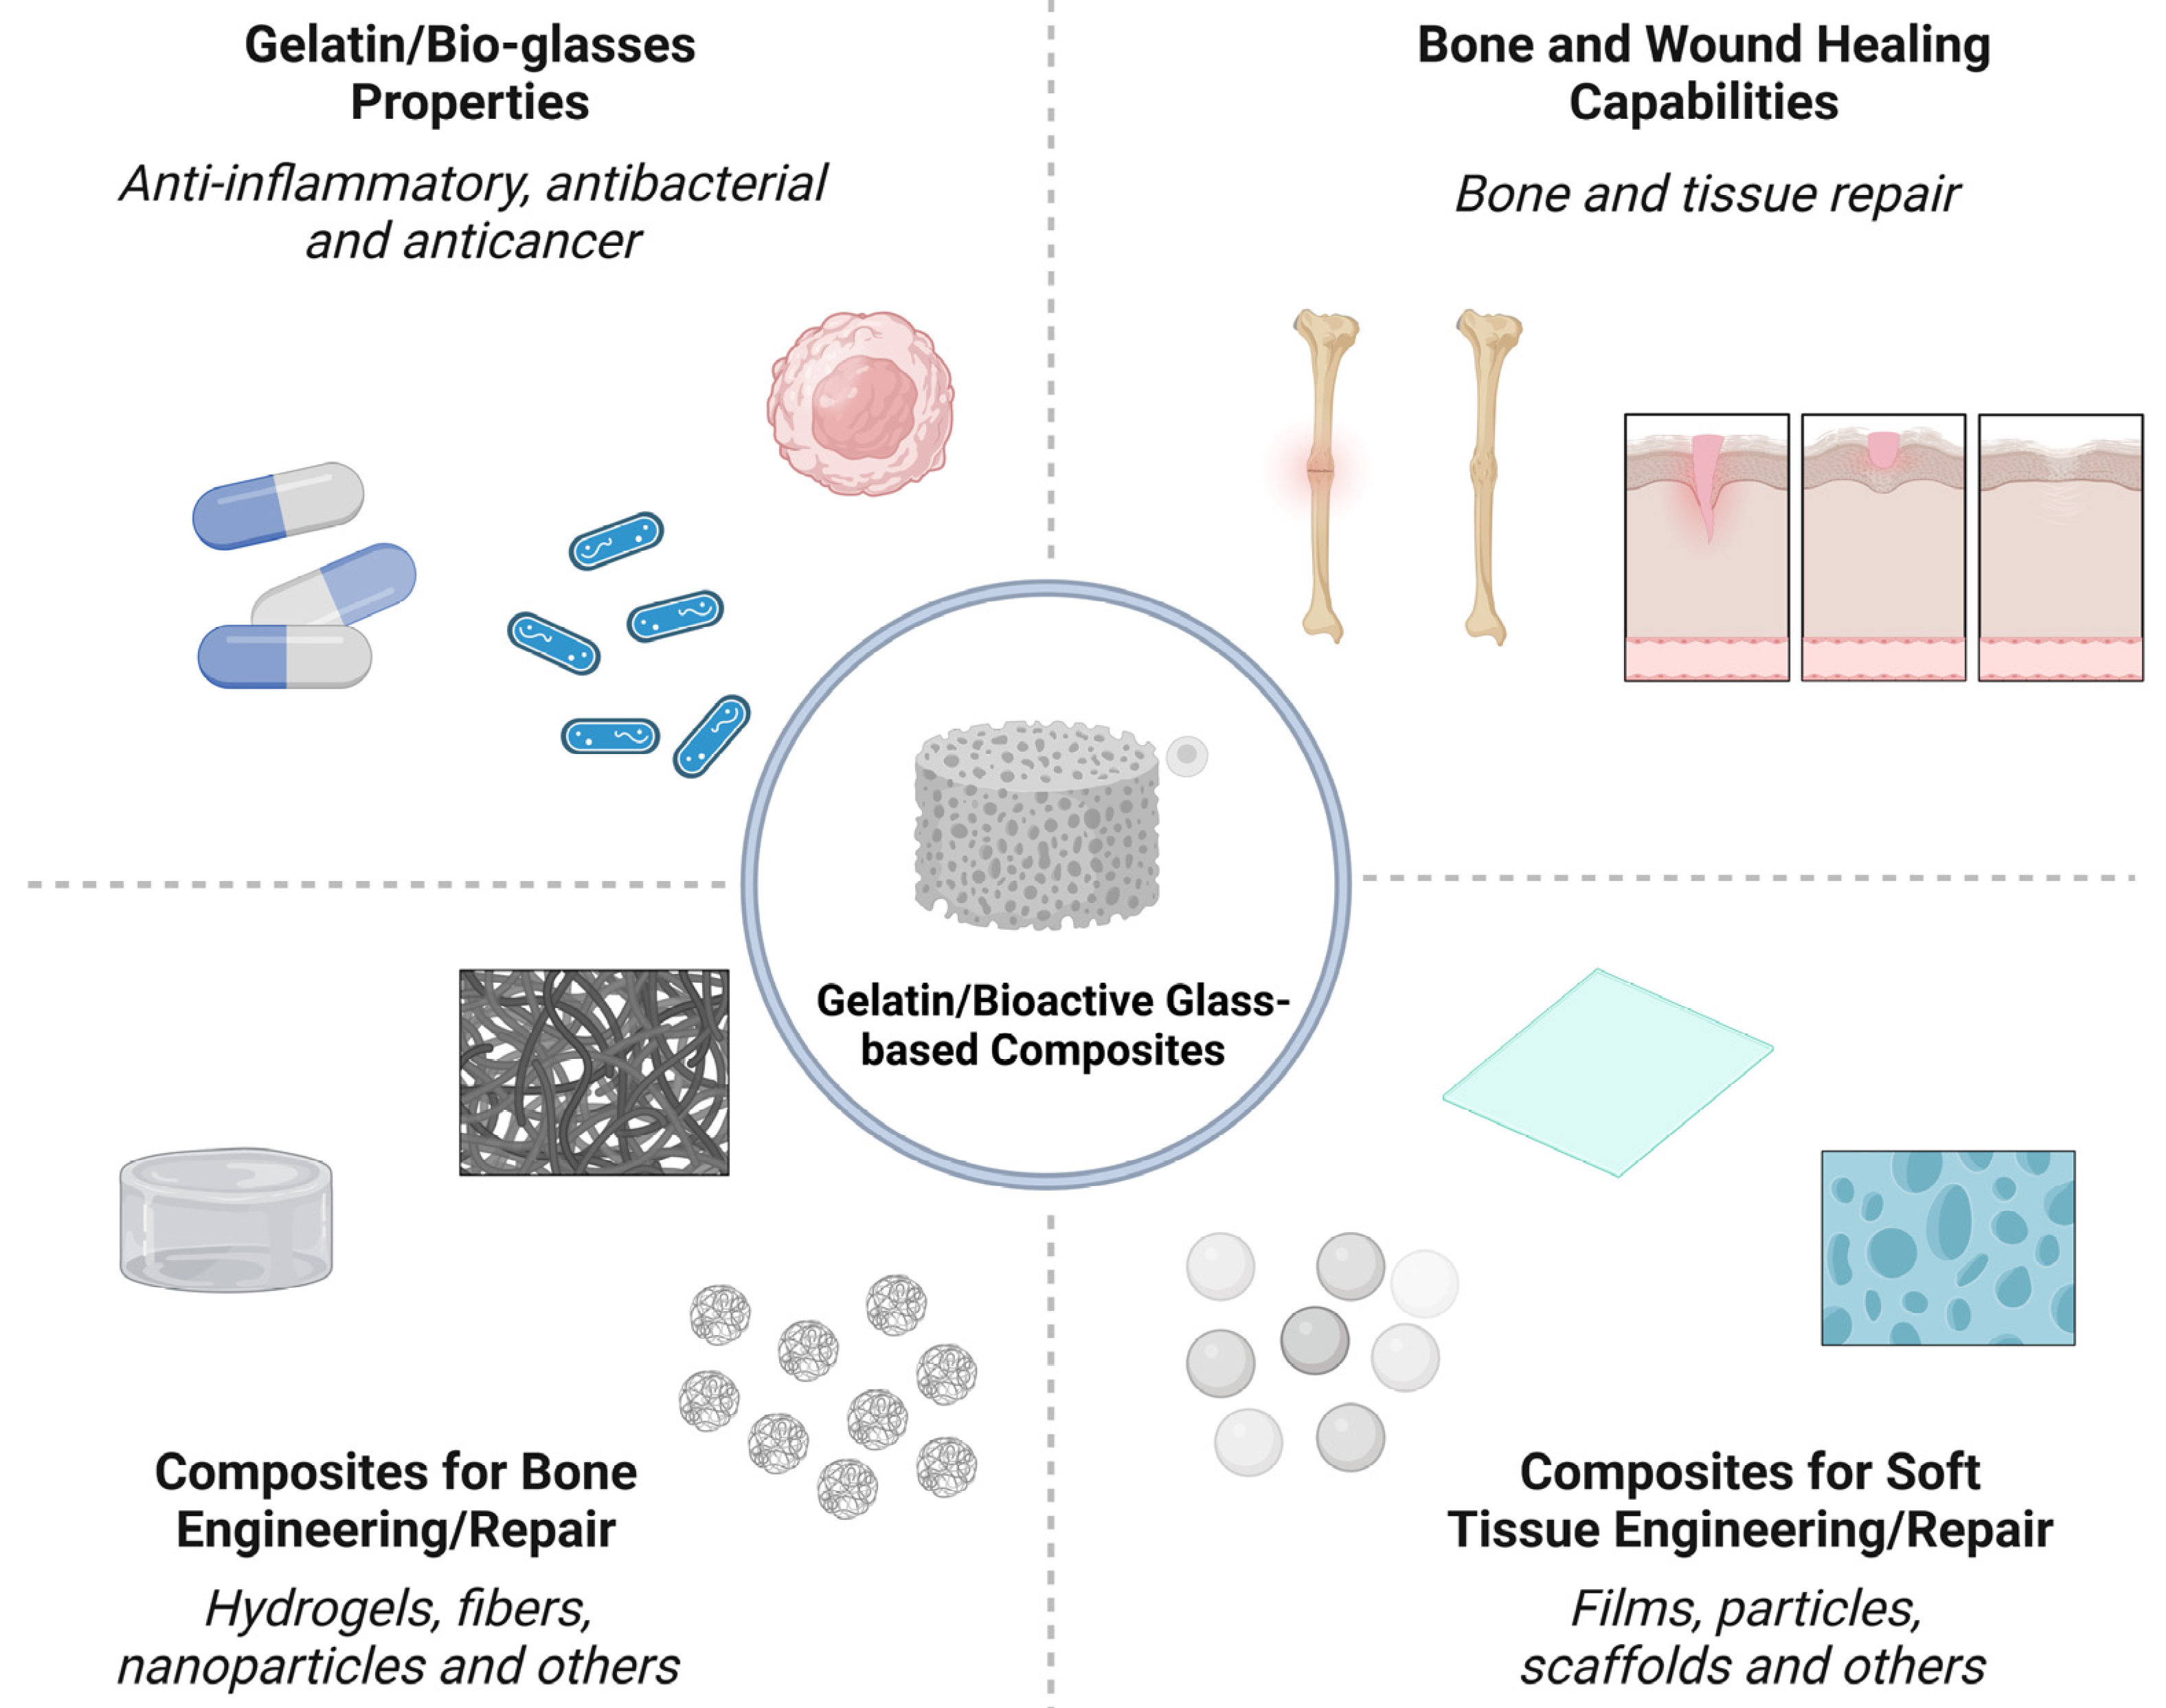

2. Bone Engineering

2.1. Bone Healing Mechanisms